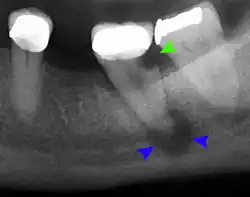

Once a person is having symptoms related to Gigantiform cementoma it is suggest to seek medical attention. The health providers that can help would be a Dentist, Oral Surgeon, Oral Pathologist, and Prosthodontist. A dentist can do an exam and take x-rays to evaluate symptoms and to be able to refer the patient to the correct specialist. An Oral Surgeon are specialized with surgical procedures related to the mouth, jaw and the face. An Oral Pathologist is able to help with diagnosis by examining the tissues samples in order to diagnosis and treat diseases related the jaw, and mouth. Prosthodontist are able to aid with the missing teeth. The doctors specialize with dental prosthetics. In order to diagnosis a patient with Gigantiform cementom there has to be X-ray done that provides the doctor with the view of the jaw and the teeth to identify the tumor and to also be able to see the size of the tumor. There are different types of X-rays that can be done which are the Panoramic Radiograph and Cone Beam Computed Tomography (CBCT). Biopsy may be suggested by an Oral Surgeon to be able to collect tissues from the tumor to get samples for histological examine, this is necessary to confirm diagnosis. Blood test can also be done to confirm diagnosis.